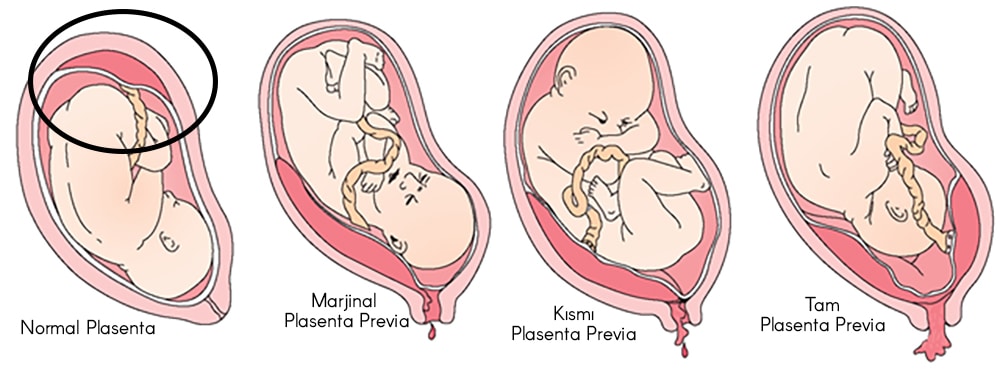

Plasenta previa, plasenta ile serviks (alt segment) arasındaki ilişkiye göre üç gruba ayrılır:

Tam (total) plasenta previa (%20-45): Plasenta rahim ağzını tamamen kapatmıştır.

Kısmi (parsiyel) plasenta previa (%30): Plasenta rahim ağzının bir kısmını kapatmıştır.

Marjinal plasenta previa (%25-50): Plasenta rahim ağzına yakındır ama kapatmaz.

Bazı gebeliklerde ise plasenta kenarı rahim alt segmentine yerleşmiştir, ancak doğum kanalını kapatmaz. Bu tür yerleşim gösteren plasentaya “alt segment yerleşimli plasenta” adı verilmektedir ve aslında bu durumun klinik olarak bir önemi bulunmamaktadır. Gününü doldurmuş gebeliklerde plasenta previaya binde 3-5 oranında rastlanır. Daha önceden sezaryen geçirmiş olanlarda ise risk 1.5-5 kat artar ve geçirilmiş sezaryen sayısına paralel olarak bu oran %10’a kadar çıkabilir.